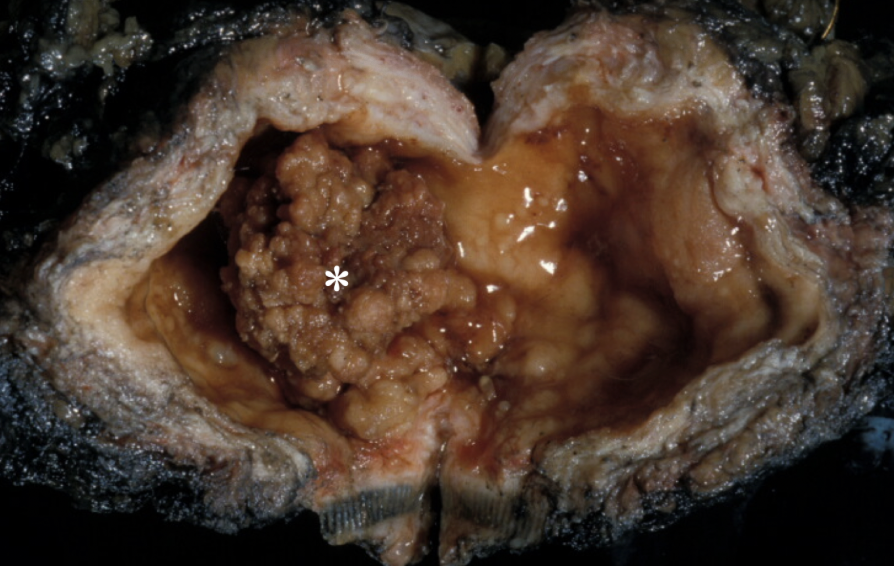

most common neoplasm of the bladder

papillary

flat (CIS)

two types of noninvasive urothelial cell lesions that can become invasive

polypoid urothelial carcinoma of the bladder

papillary urothelial neoplasms of low malignant potential (PUNLMP)

thicker urothelium with greater density of cells

larger than papillomas

indistinguishable from cancers

can recur but progression rare

invasive UCC

painless hematuria, frequency, urgency, dysuria

occasional ureteral orifice obstruction may lead to pyelonephritis or hydronephrosis

depth of invasion into bladder wall

most important prognostic factor for invasive UCC and determine treatment modality

painless hematuria

most common symptom of bladder cancer